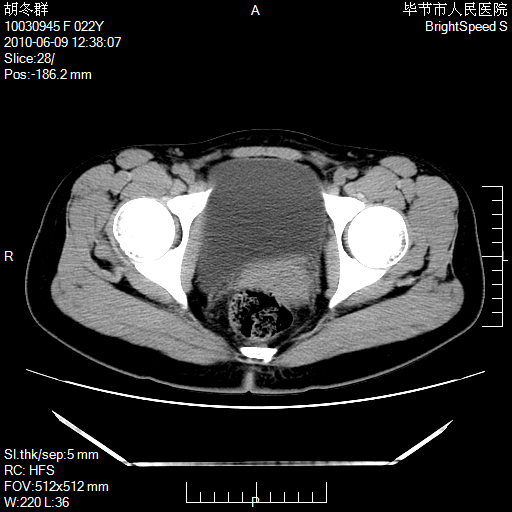

患者23岁,发现腹部包块3月。

我当时考虑重复膀胱,但我错得很厉害,我不明白,囊肿排尿后为什么能到膀胱位置。

囊性病变,可以增强检查,不除外输尿管囊肿

盆腔内囊性占位性病变;考虑左侧卵巢囊腺瘤。

有分隔、壁薄,支持考虑左侧卵巢囊腺瘤。

左侧卵巢浆液性囊腺瘤。

有分隔、壁薄,支持考虑左侧卵巢囊腺瘤。排尿后,膀胱缩小,由于重力作用,肿块下移就到了膀胱位置,很好理解。